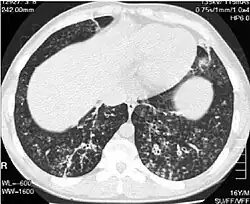

O diagnóstico da panbronquiolite difusa requer a análise dos tecidos do pulmão e dos bronquíolos, o que pode exigir uma biópsia ou uma tomografia computadorizada (TC) de alta resolução dos pulmões. Os critérios diagnósticos incluem inflamação grave em todas as camadas da bronquíolos respiratórios e lesões do tecido pulmonar que aparecem como nódulos dentro do bronquíolo terminal e respiratório em ambos os pulmões. Os nódulos na panbronquiolite aparecem como caroços opacos quando vistos em radiografias do pulmão e podem causar obstrução das vias aéreas, o que é avaliado por um teste de função pulmonar. A radiografia de tórax também pode revelar dilatação das passagens bronquiolares, outro sinal da doença. A tomografia mostra frequentemente bloqueios de algumas passagens bronquiolares por muco, que é referido como padrão em "árvore em brotamento". A hipoxemia, outro sinal de insuficiência respiratória, é revelada através da medição do conteúdo de oxigênio e dióxido de carbono do sangue, usando um exame de sangue chamado de gasometria arterial. Outros achados observados na panbronquiolite incluem a proliferação de linfócitos (glóbulos brancos que combatem as infecções), neutrófilos e histiócitos espumosos (macrófagos teciduais) no lúmen do pulmão. Bactérias como H. influenzae e P. aeruginosa são também detectáveis, com a última se tornando mais proeminente com a progressão da doença. O nível de glóbulos brancos, bactérias e outros conteúdos celulares do sangue podem ser medidos através de um hemograma completo. Níveis elevados de IgG e IgA (classes de imunoglobulinas) pode ser vistos, bem como a presença de fator reumatoide (um indicador de auto-imunidade). Hemaglutinação, uma aglomeração de células vermelhas do sangue em resposta à presença de anticorpos no sangue, pode também ocorrer. Neutrófilos, beta-defensinas, leucotrienos e quimiocinas também pode ser detectados no fluido do lavado broncoalveolar injetado então removido das vias aéreas bronquiolar de indivíduos com a doença, para avaliação.